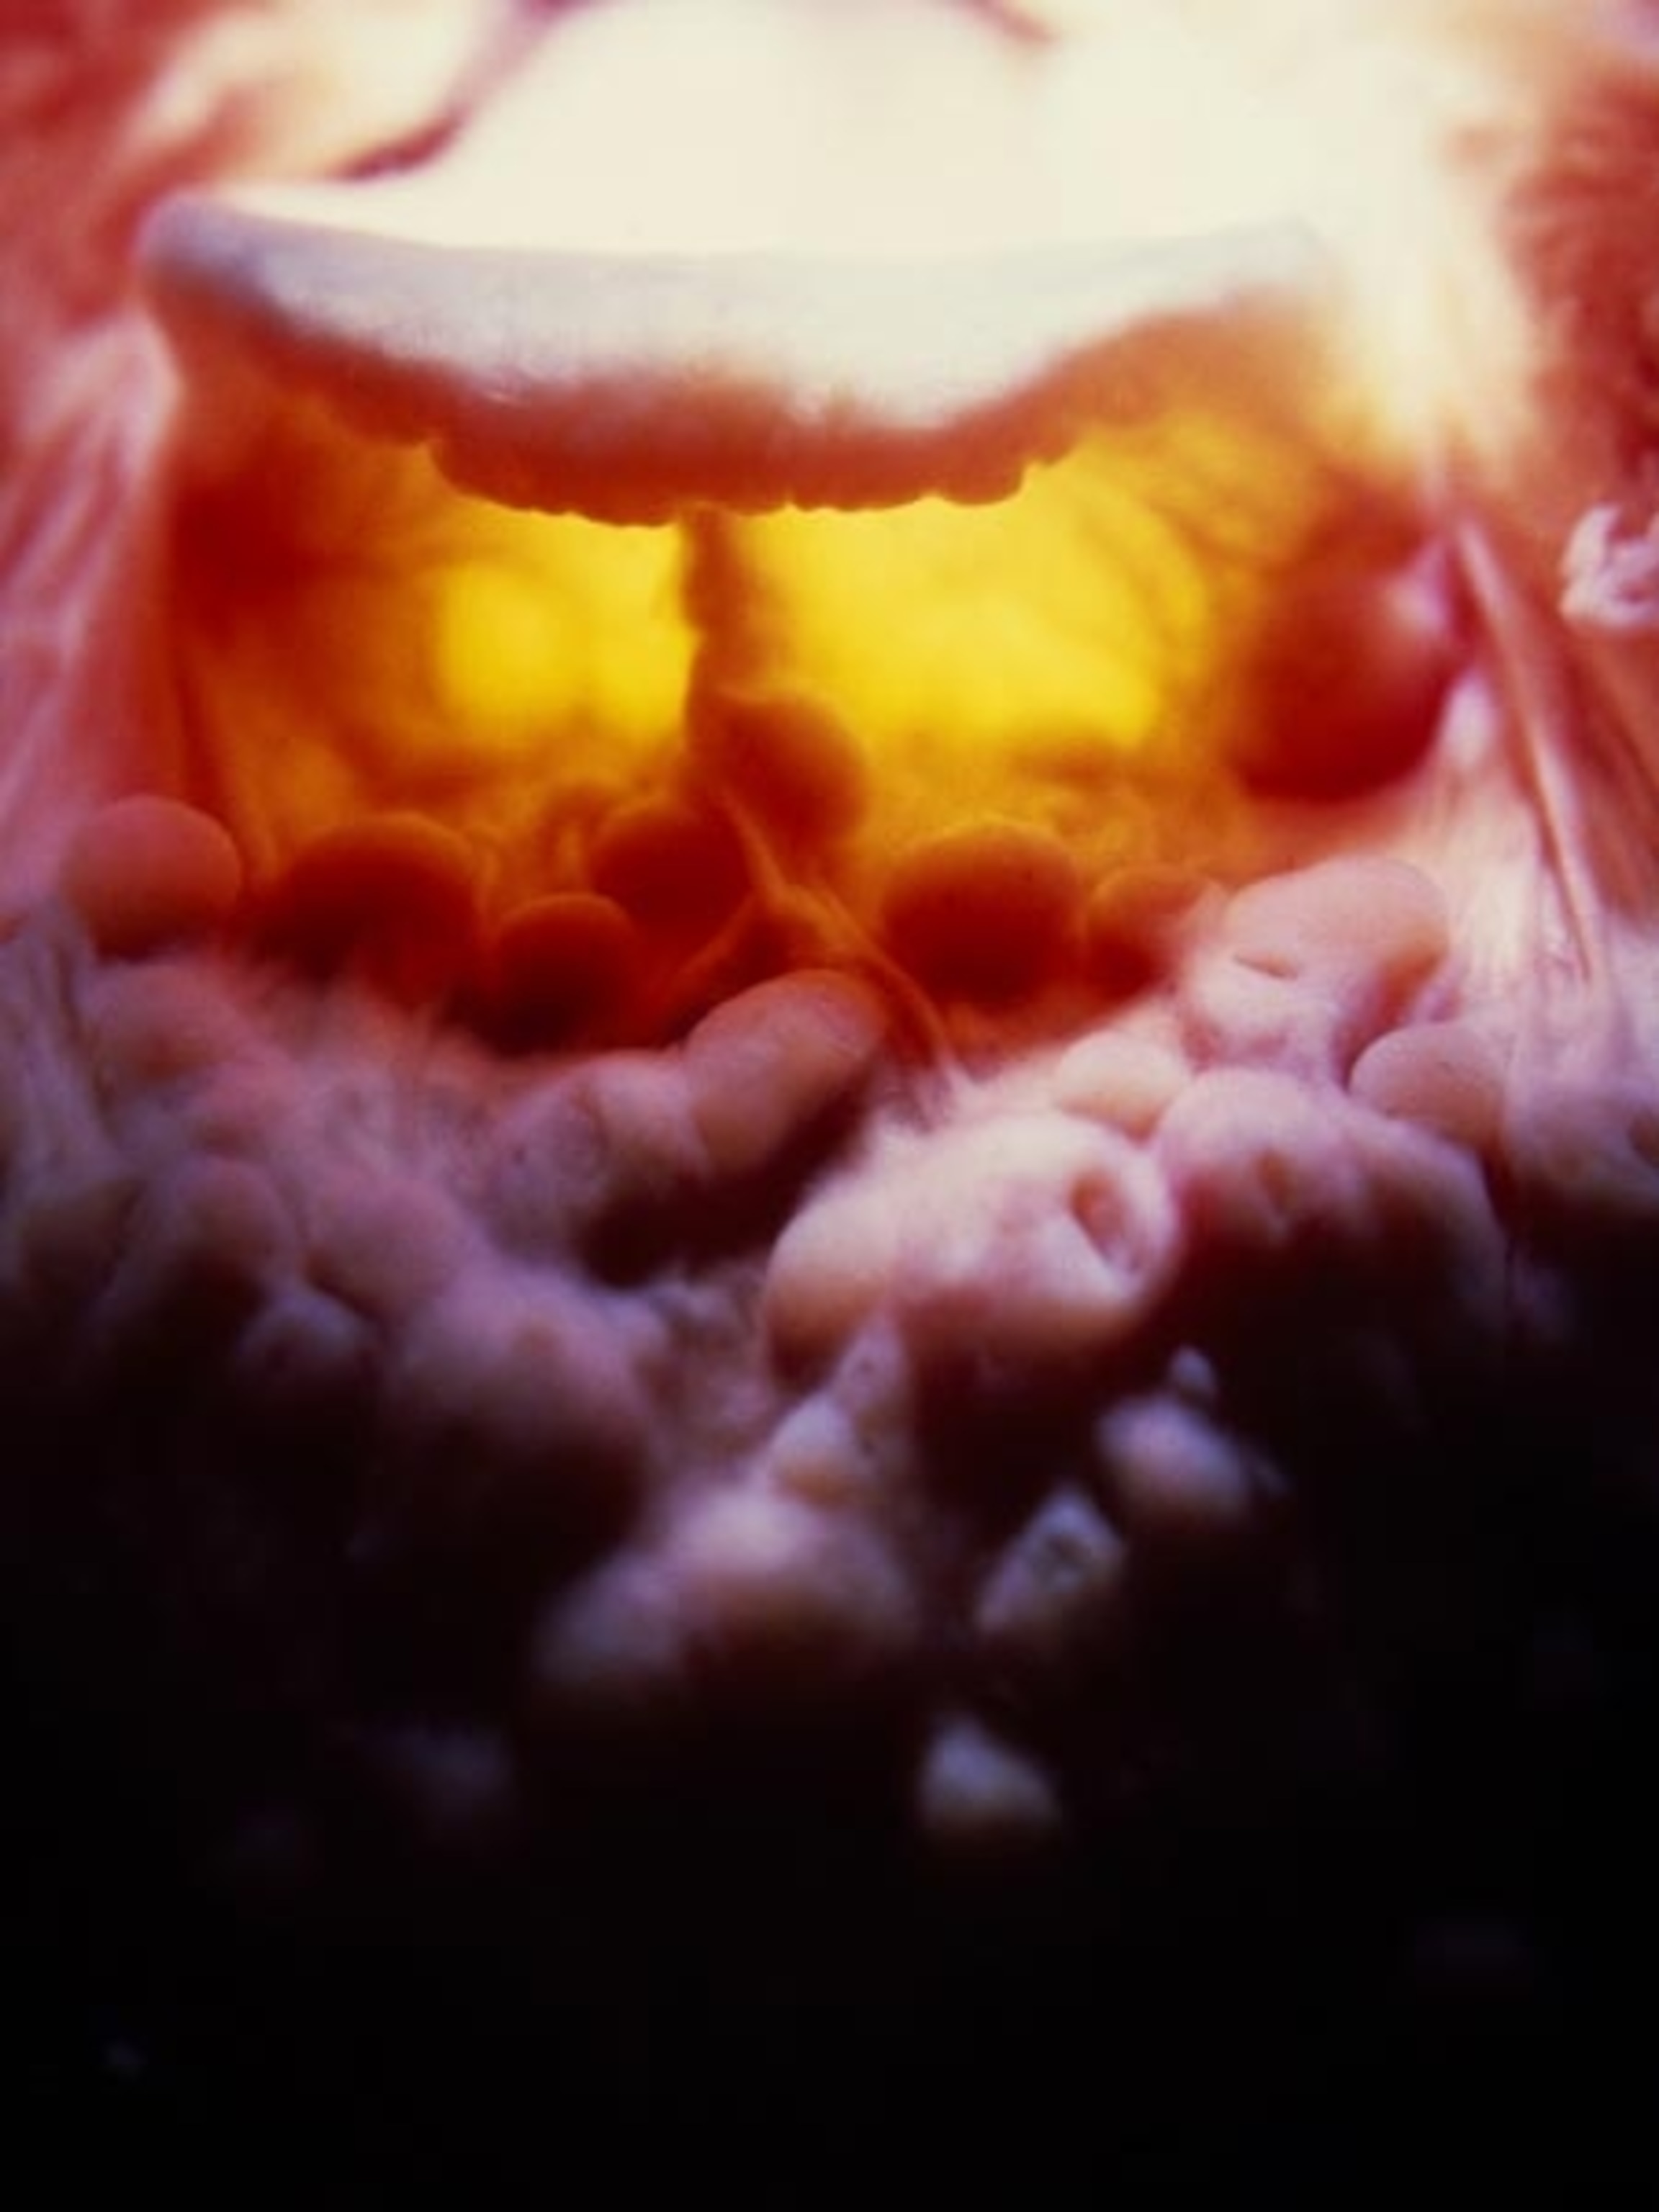

Measuring about 20 feet (6 meters) in length, the small intestine is where the major digestion and absorption of nutrients take place. These nutrients are taken into the bloodstream, via millions of tiny, fingerlike projections called villi, and transported to the liver.